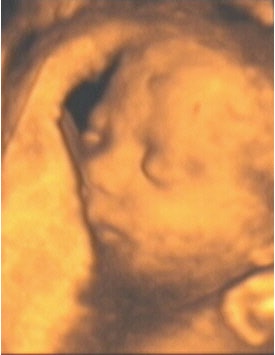

![]() |

| Figure 11, a 3-D ultrasound image of a fetal face at 27 weeks gestation. Image courtesy of Stefano Ciatti, M.D. |